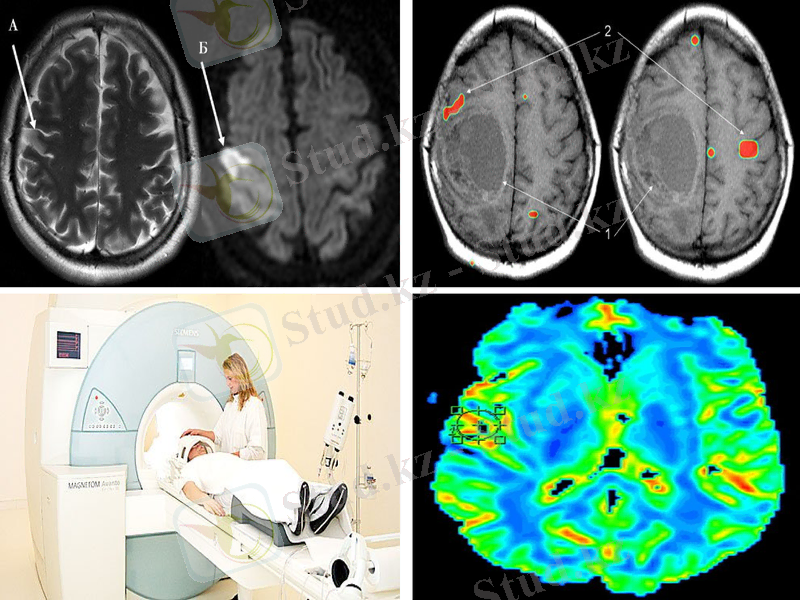

Ең алғаш рет МРТ бас миын зерттеулерде қолданылды, ол неврологияның әрі қарай дамуына септігін тигіді. МРТ арқылы жасуша мембранасындағы молекулалардың қозғалысын бағалауға болады(Диффузионная МРТ ), капилляр арқылы қанның жылжуын, метаболиктердің концентрациясын анықтауға болады(Перфузионная МРТ ) . Функционалды МРТ арқылы қозғалыс және сөйлеу орталығын анықтауға болады. Ишемиялық инсультқа ие науқастың МРТ ми инфарктысының алдын ала бола ма жок па болжам жасай алады.